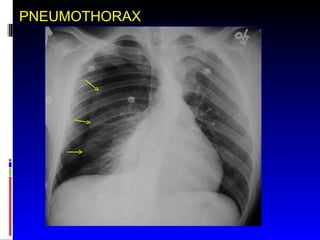

PNEUMOTHORAX

• #33 Air in the pleural space separates the visceral and parietal pleura. This limits effective ventilation of the lung.